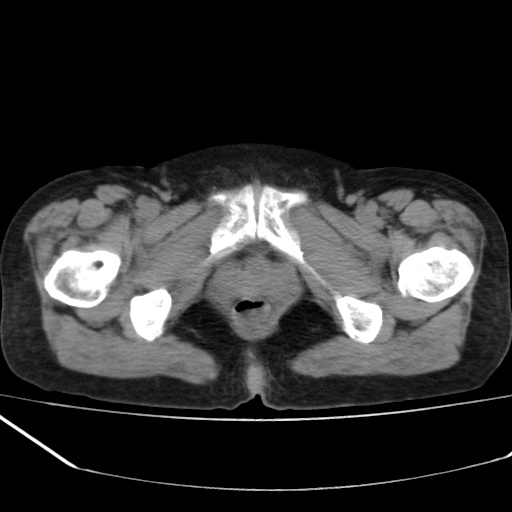

病人不肯增强,是不是膀胱右前方那一个

盆腔右前壁囊性占位,右耻骨轻微骨质吸收.性质选定,建议增扫或病理!!!!!

我只好报盆腔右前壁囊性占位,性质选定,建议增扫或病理.

膀胱右前方占位

病史?临床表现?膀胱右前方囊性占位,边缘光整,考虑良性,建议结合b超检查,既然要做手术,等手术结果吧,只是觉得手术仓促了些。

膀胱右前壁囊性占位,性质难定,要做手术,那就等手术结果吧.